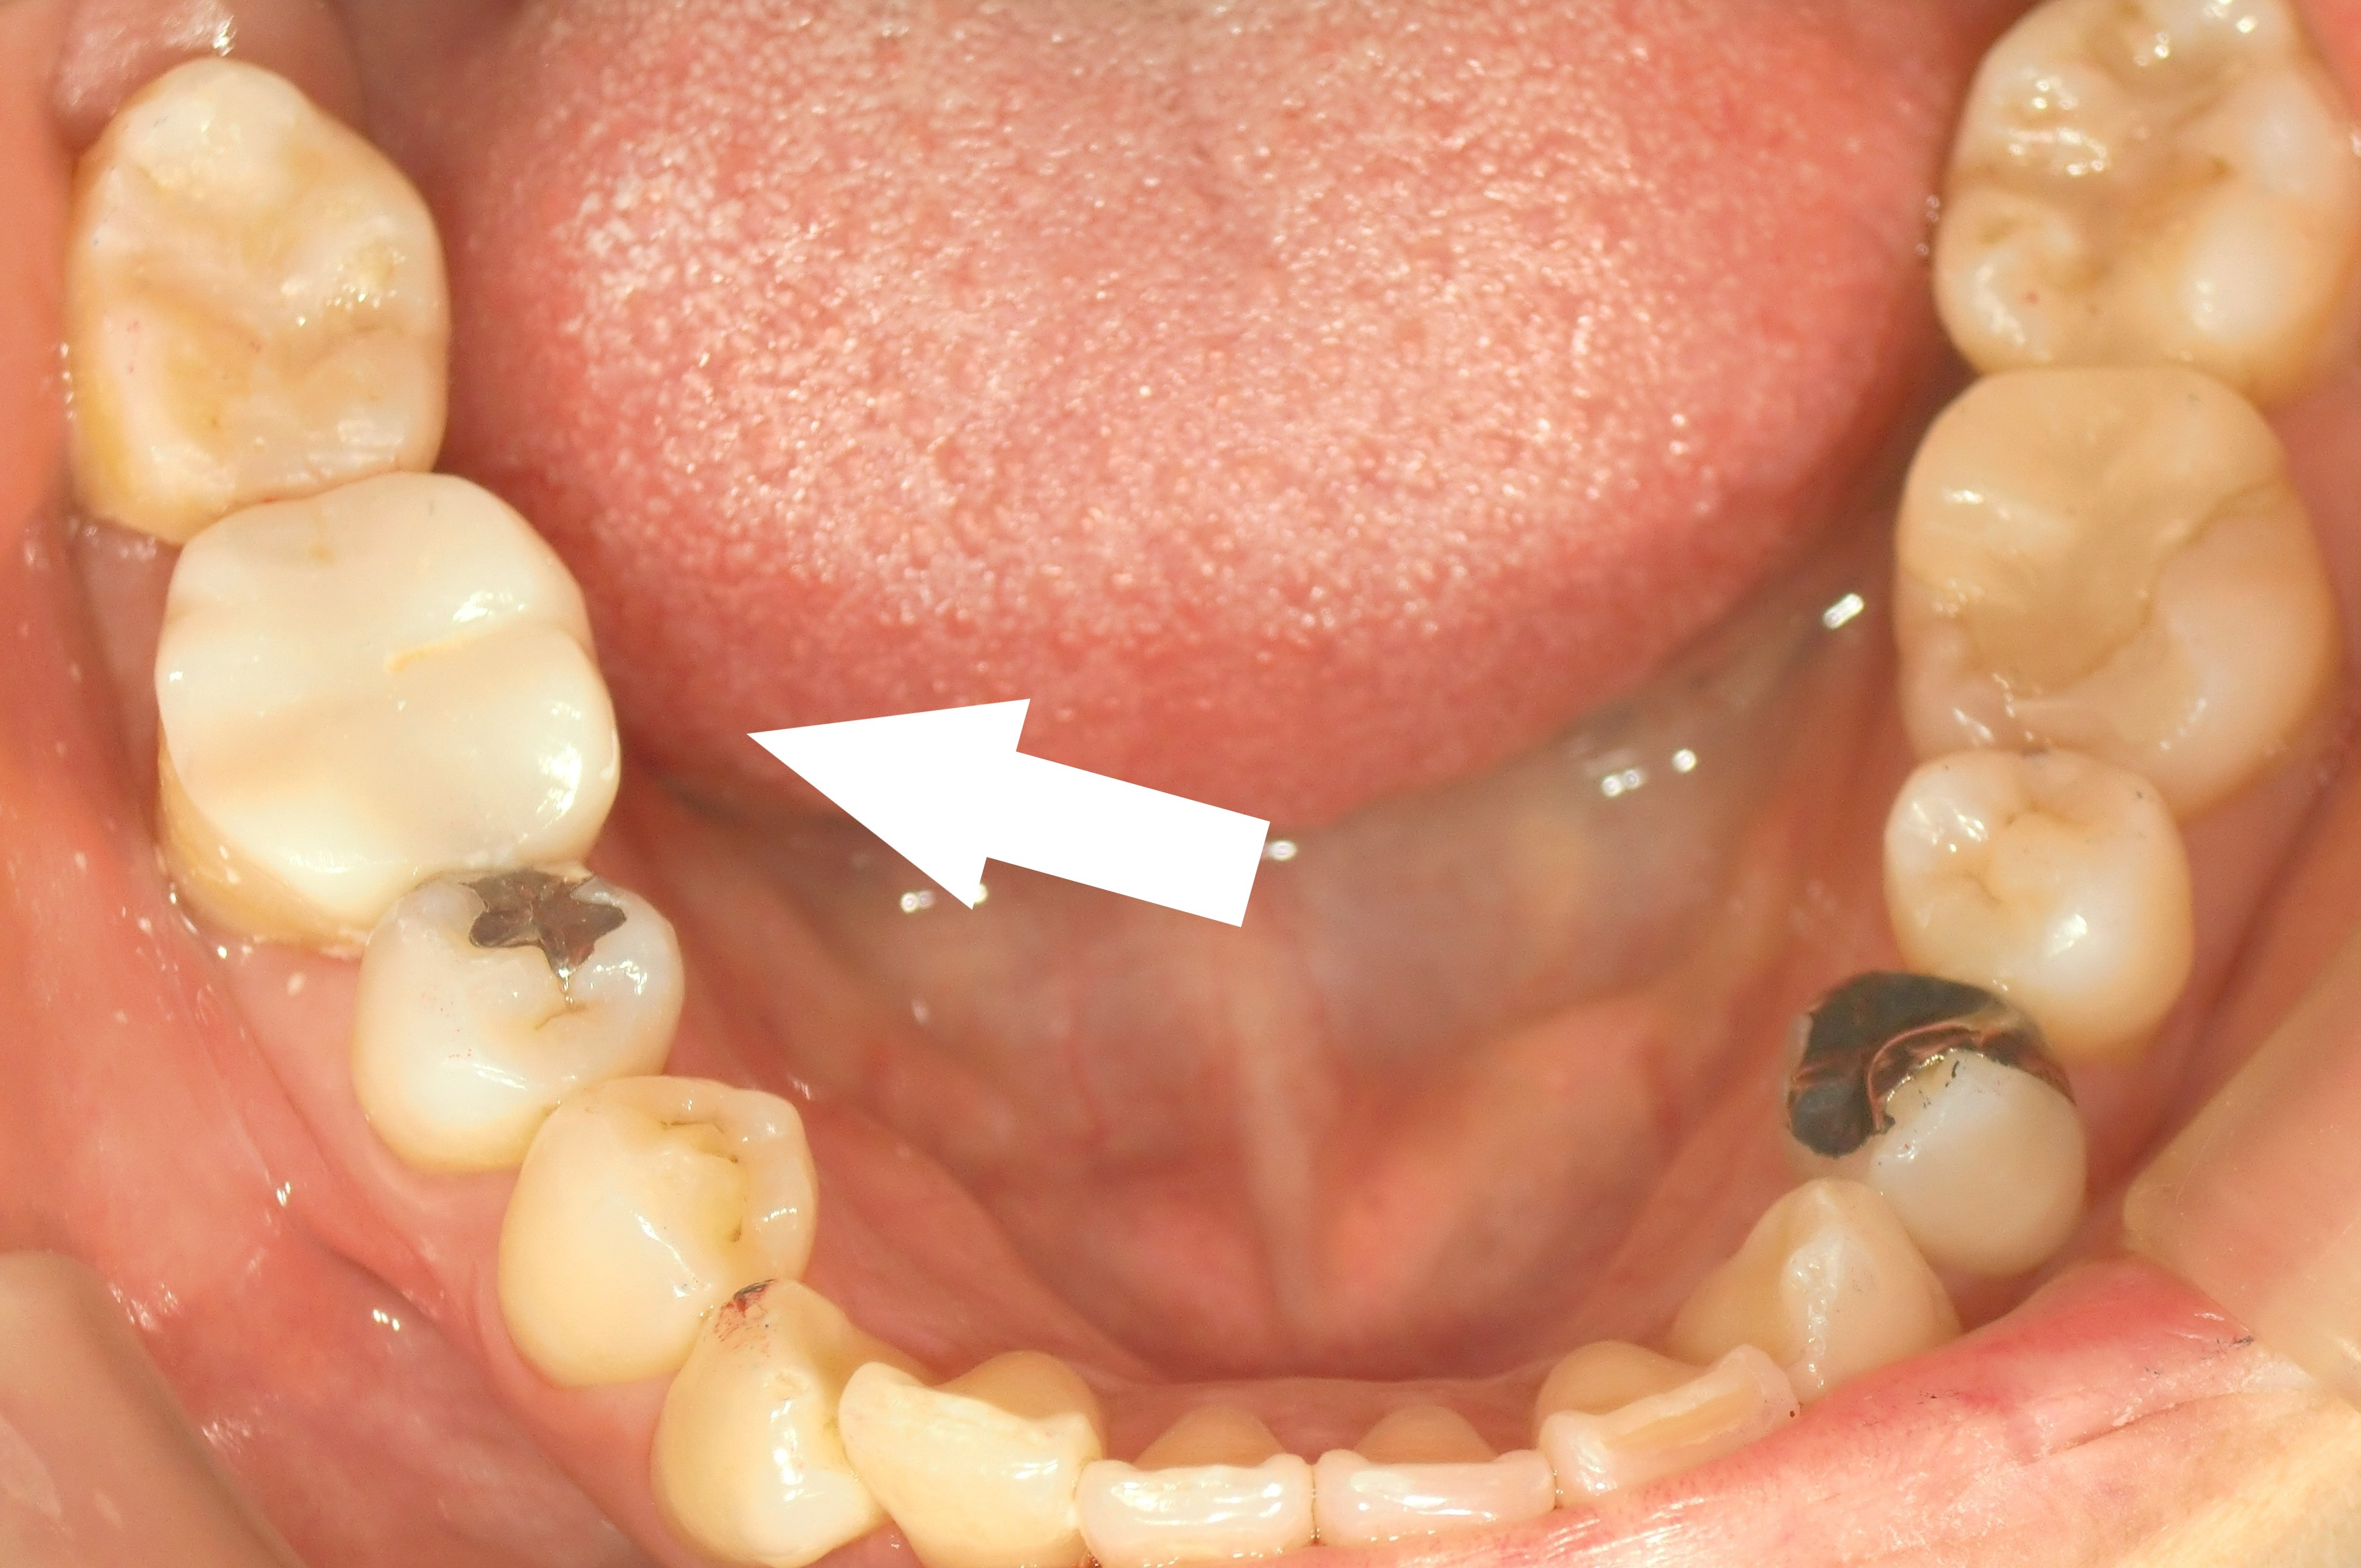

田原本町 ジルコニアオンレー 40代 「右下奥歯の痛みが続いていた」

術前 → 術後

右下の歯の神経の痛みで他院にかかっていましたが、被せや知覚過敏の治療で様子みてもらう状態で一ヶ月程たち、急な痛みから、レントゲン、CT、根管治療の設備が整っていて、治療をしっかりしてくれている病院を探していました。ホームページで拝見して通院させて頂き、初日の検査で状態を説明して頂き、迷うことなく神経を取ってもらおうと思えて安心して治療して頂けました。スタッフの方や先生にもいつも丁寧に接してもらい、右下の歯だけでなく虫歯も見つけてもらい、きちんと治療して頂けて良かったです。